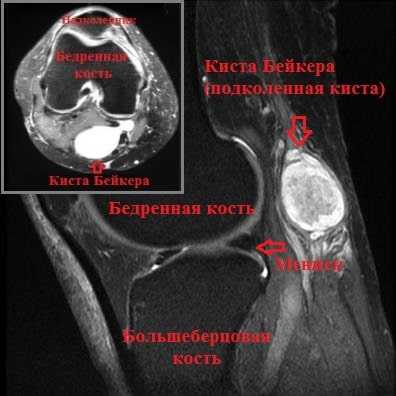

По данным УЗИ коленного сустава: признаки кисты заднего отдела коленного сустава размером 9*5*3 см. По данным МРТ коленного сустава: признаки синовиальной кисты заднего отдела сустава размером 8,5*4,5*3 см, дегенеративного комбинированного разрыва внутреннего мениска и хондромаляции (размягчения хряща) III степени.

Подколенная киста или киста Бейкера представляет собой мягкое, безболезненное образование, заполненное жидкостью и располагающееся в подколенной ямке. Киста Бейкера или подколенная киста чаще всего встречается у пациентов перенесших травму колена или страдающих артрозом коленного сустава.

Избыточный объем синовиальной жидкости продавливает слабую заднюю капсулу сустава в подколенной области, и со временем формируется киста Бейкера. Можно сказать, что киста Бейкера — это не что иное, как выпячивание задней стенки капсулы сустава.

Клинически это проявляется мягким образованием по задней поверхности коленного сустава в подколенной ямке. Впервые данное образование под коленом описал врач Бейкер, поэтому оно в последствие получило его имя.

Однако наиболее современным и точным методом обследования коленного сустава в общем и кисты Бейкера в частности является МРТ. На МРТ можно оценить размер кисты, ее точную локализацию, а также оценить плотность ее содержимого.